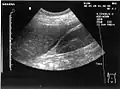

Ultrasound of liver (left side of the image) and right kidney (right side of the image) and Morison's pouch, not containing fluid- Abdominal CT, showing Morison's pouch as the dark margin surrounding the right kidney (at lower left corner of image)